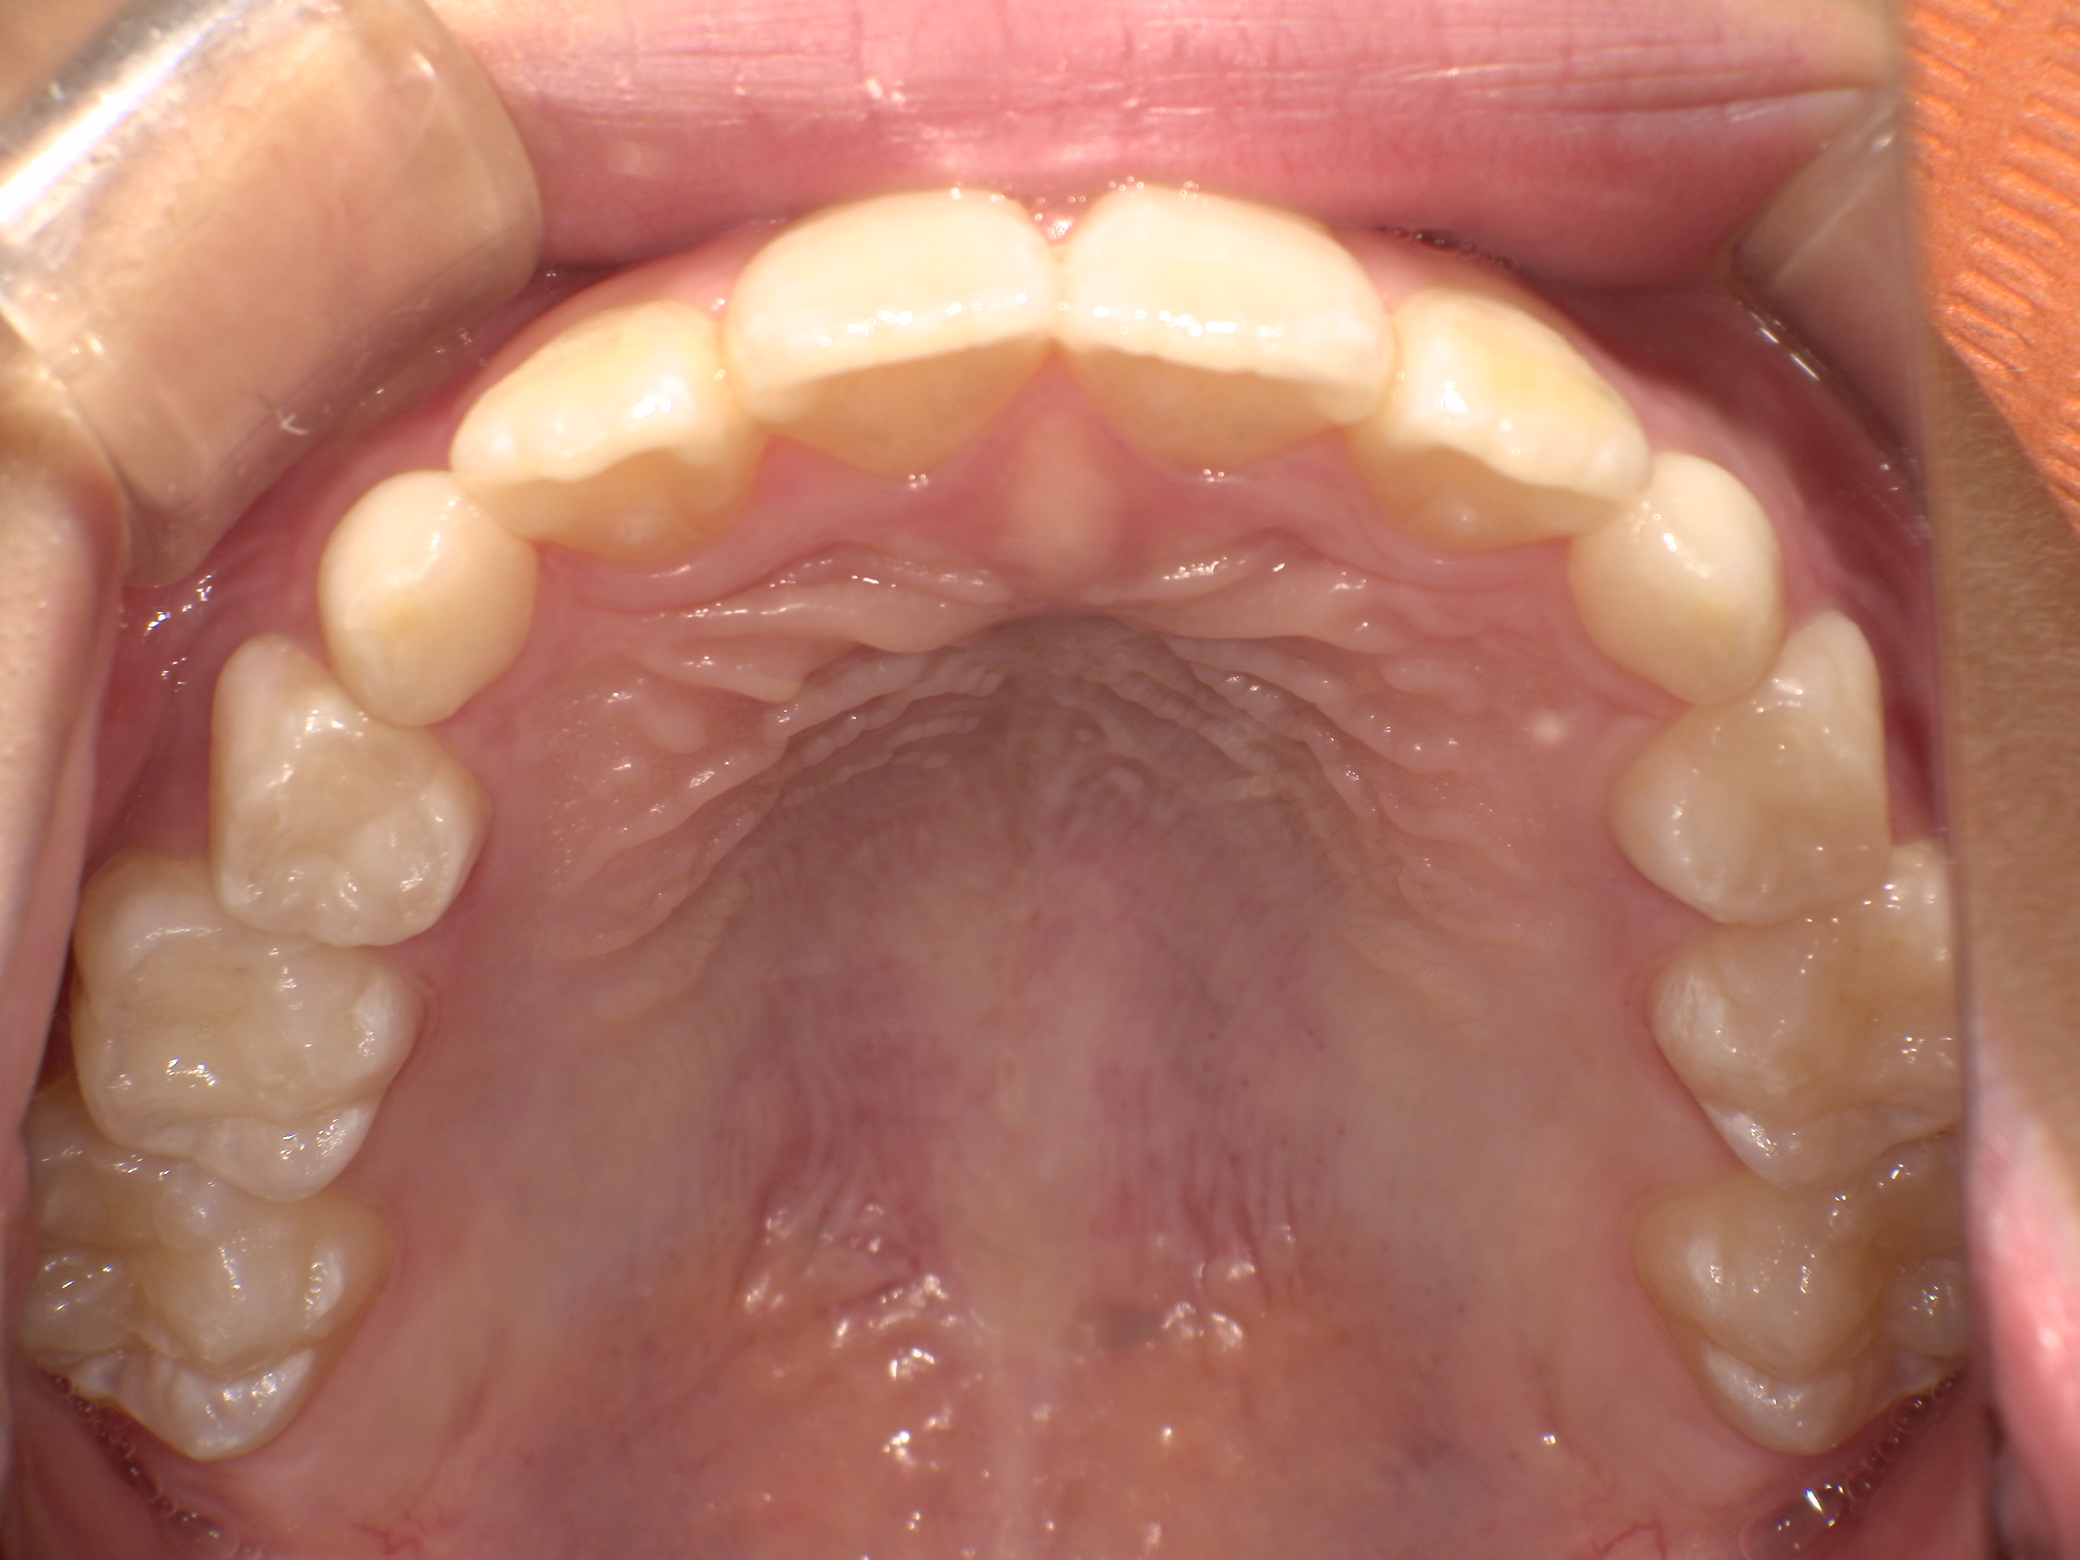

バイオネーターの症例

主訴 | 出っ歯が気になる |

---|---|

治療内容 | バイオネーター |

治療期間 | 1年11ヶ月 |

治療費用 | 330,000円(税込) |